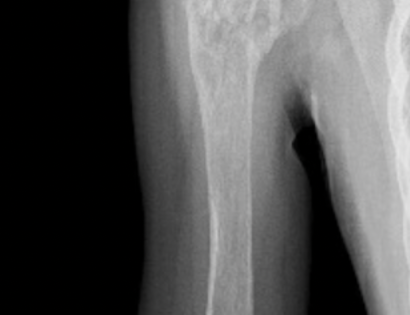

X-Ray of tumor

This is an X-ray of the tumor in the bone. The tumor is located in the right shoulder (towards the top of the image).